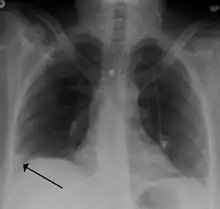

- Chest X-rays are often done on people with shortness of breath to help rule-out other causes, such as congestive heart failure and rib fracture. Chest X-rays in PE are rarely normal,[67] but usually lack signs that suggest the diagnosis of PE (for example, Westermark sign, Hampton's hump).